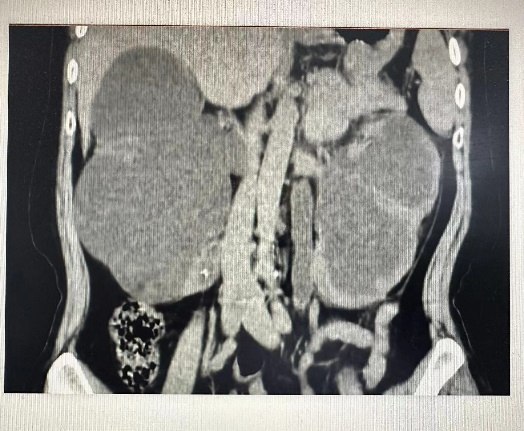

外四科皮生明主任查看患者,為避免感染及膿毒血癥進(jìn)一步加重,立即安排術(shù)前相關(guān)檢查及準(zhǔn)備,一切準(zhǔn)備就緒,急診行“雙側(cè)經(jīng)皮腎穿刺造瘺”術(shù),經(jīng)過(guò)1個(gè)多小時(shí)手術(shù)及時(shí)解決了患者可能出現(xiàn)的病情變化及并發(fā)癥,患者術(shù)后12小時(shí)各項(xiàng)感染指標(biāo)控制,腎功能改善,肌酐由術(shù)前264μmol/L降至114μmol/L。

(術(shù)前) (術(shù)后) 術(shù)后,張阿姨和家屬及時(shí)將5000元墊付住院費(fèi)還給了湯醫(yī)生,查房時(shí),張阿姨拉著醫(yī)生的手激動(dòng)的說(shuō):我們兩口子都不懂,要不是你們積極幫助,我怎么可能那么順利及時(shí)得到手術(shù),去哪里找這么好的醫(yī)生,太謝謝你們了,我們好好配合治療,聽(tīng)你們安排,就盼著早點(diǎn)恢復(fù)好回老家過(guò)年。 這只是外四科日常工作的縮影,全體醫(yī)護(hù)人員將患者的就醫(yī)感受,就醫(yī)體驗(yàn)牢記于心,力所能及為患者解決困難和問(wèn)題。